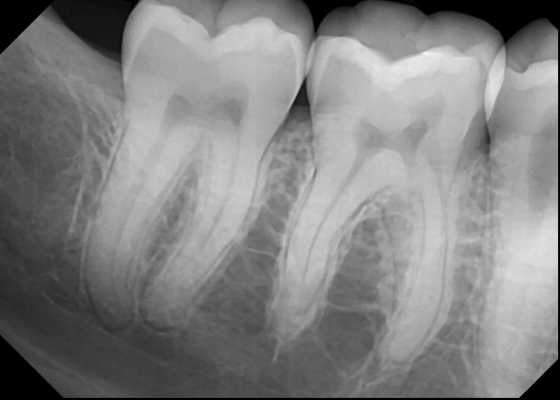

Evaluate #30

Widened PDL

Pulpal Disease

Evaluate #31

Normal PDL

Superimposed Anatomy

Notice other radiographic Features?